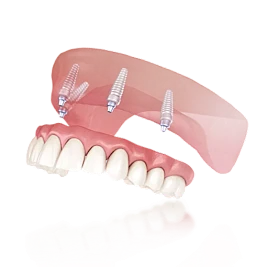

- Протезирование зубов врачом высшей категории с точной посадкой и естественной эстетикой

- Коронки и протезы на имплантах с применением микроскопа для максимальной точности

Полный пластиночный акриловый

от 54 000 ₽